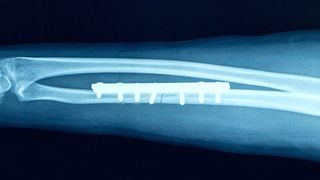

Schrauben verursachen bei der Behandlung von Knochenbrüchen immer wieder Probleme, etwa weil sie nicht genügend Stabilität verleihen oder sogar angrenzende Gelenke verletzen. Die Lösung: maßgeschneiderte Knochenplatten. „Heute werden Standard-Platten oft noch während des chirurgischen Eingriffs zurechtgebogen, damit sie dem Patienten angepasst werden können“, erklärt Zumbrunn. „Man kann sich vorstellen, dass die Resultate mitunter suboptimal sind.“

Zumbrunns Idee besteht nun darin, mittels Computertomographie und 3D-Druck die Knochenplatten auf die Anatomie jedes einzelnen Patienten abzustimmen und dadurch mehr Stabilität zu erzielen. Zudem kann so festgelegt werden, wie die einzelnen Knochensplitter vor dem Eingriff möglichst optimal verschraubt werden. Vor allem aber soll die neue Methode die OP-Zeit verkürzen. Somit könnte die „fracture specific bone plate“ langfristig einen Beitrag zur Kostensenkung im Gesundheitswesen leisten.